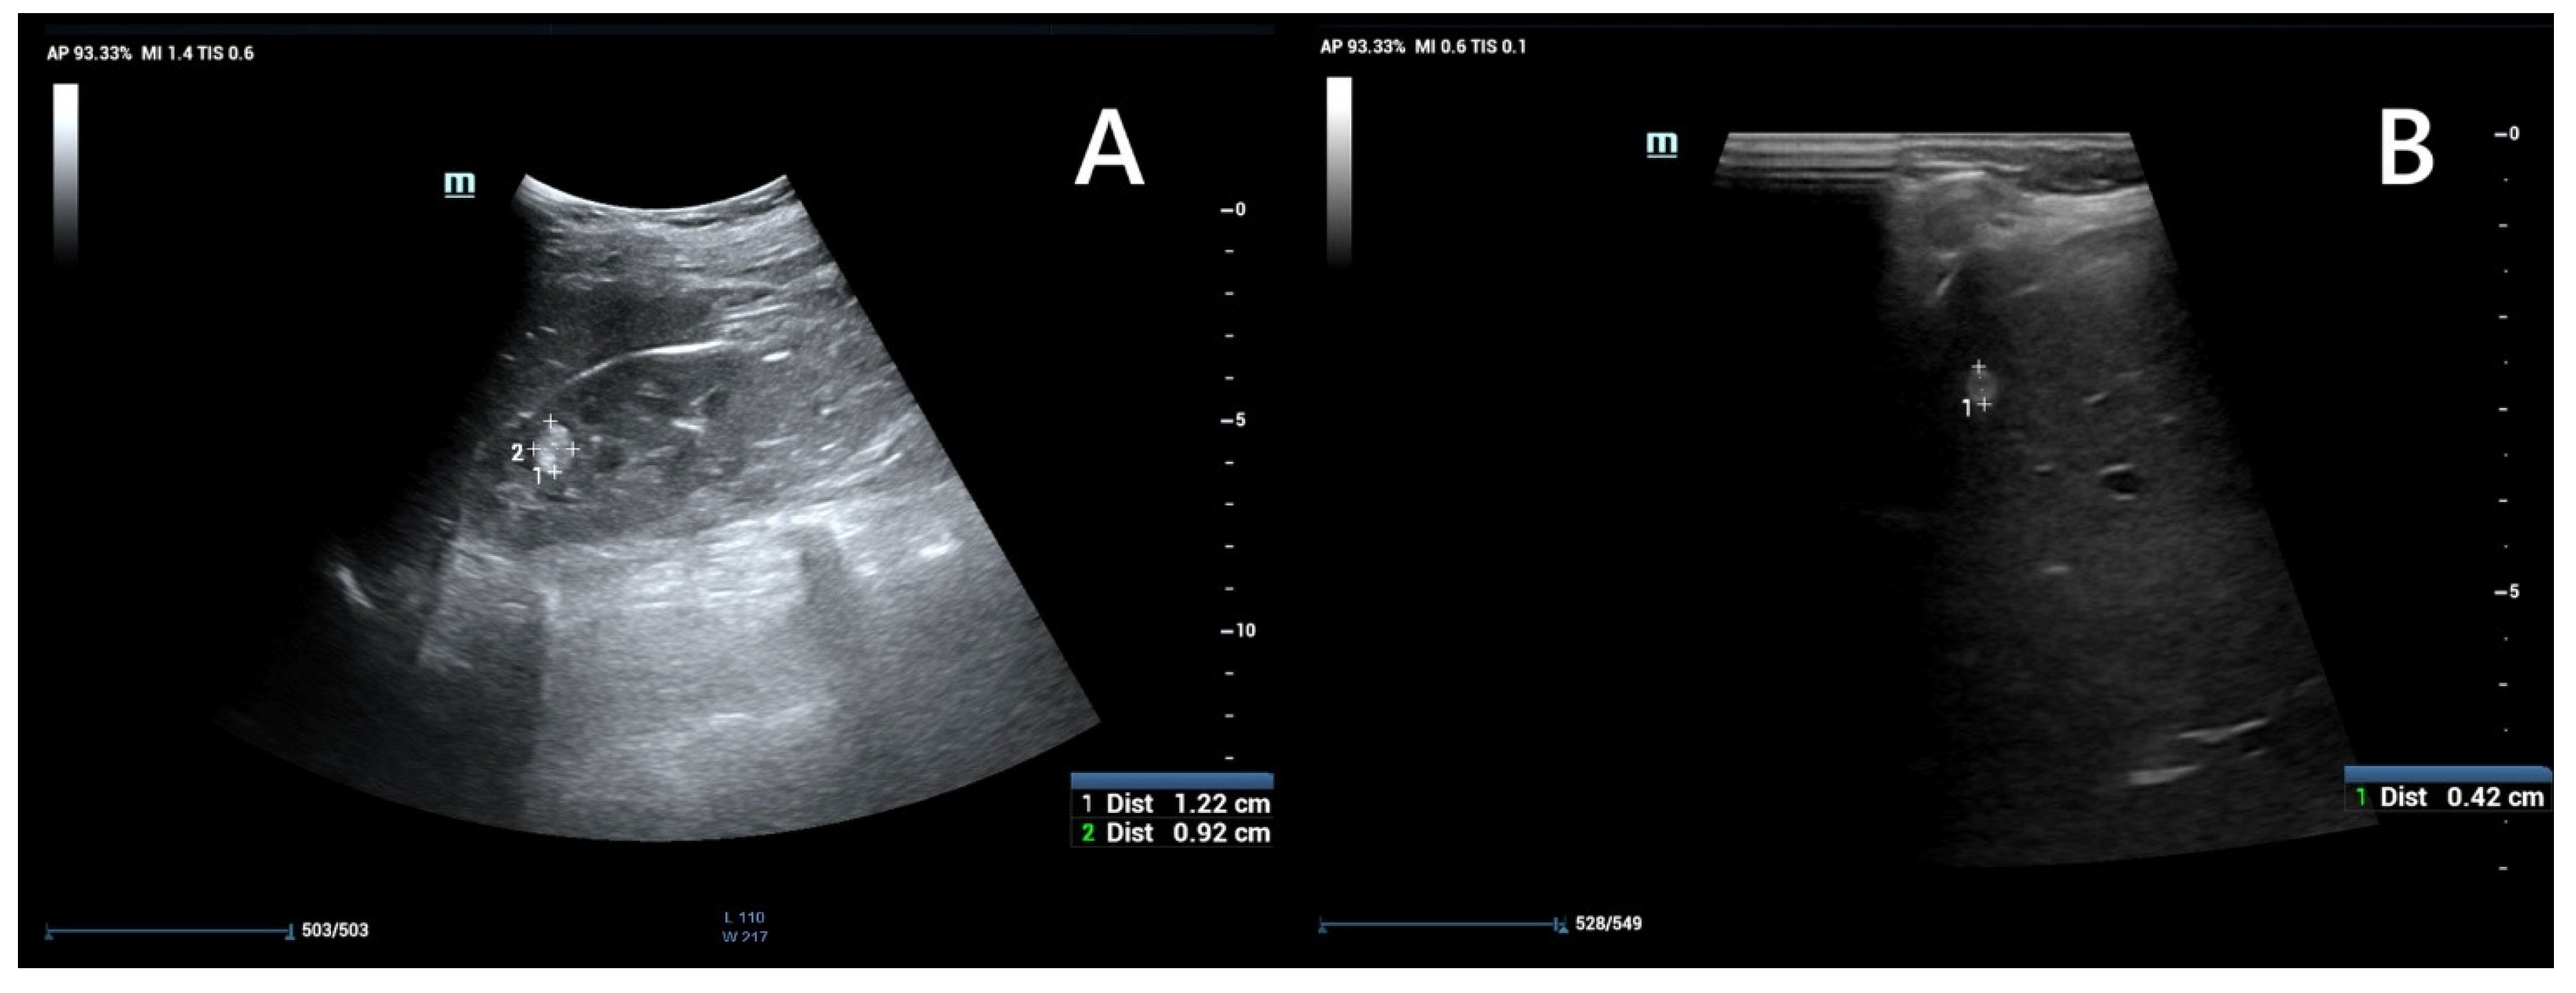

Ultrasound is widely recommended as a first diagnostic approach, helpful in detecting and monitoring lesions within kidney and other accessible parenchymal organs (Figure 4), and differentiating between their solid or cystic structure. When performed by an experienced operator, it is often sufficient for evaluating simple cysts; however in patients with large body mass, thick cystic septa, or not entirely anechoic lesion contents, further assessment with CT or MRI is recommended [44,47]. The kidney should be carefully scanned in both coronal and axial planes to ensure visualization of areas potentially obscured by artifacts, such as colonic gas or rib shadows [47].

Figure 4. An ultrasound of a 13-year-old boy. Kidney with focal lesions with features suggestive of AMLs (A). Multiple oval hyperechoic lesions within the liver—most likely AMLs (B).

AMLs in ultrasound typically appear as hyperechoic to renal parenchyma, homogeneous lesions, but their appearance can vary depending on the relative composition of fat, muscle, and vascular tissue [48]. The imaging appearance is non-specific, as up to 8% of renal cell carcinomas (RCCs) can also be hyperechoic, and confirmation by CT or MRI is recommended. However, it can provide valuable indicators: if the tumor is less than 3 cm and an acoustic shadow is present, angiomyolipoma is the most likely diagnosis. In contrast, the presence of a hypoechoic halo and intratumoral cysts suggests clear cell renal carcinoma (CCRC) [44,47,48]. Atypical or fat-poor AMLs require diagnostic evaluation with other, more advanced imaging modalities, as ultrasound images are varied and non-specific [48].